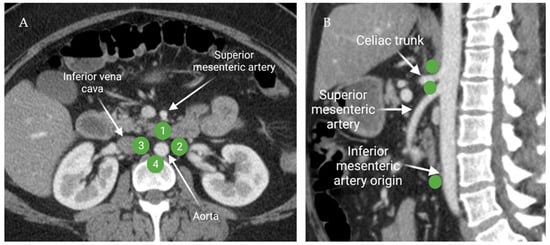

2.1.3. Peri-Aortic Lymph Node Anatomy

2.1.4. Anatomy of the Visceral/Digestive Lymph Nodes